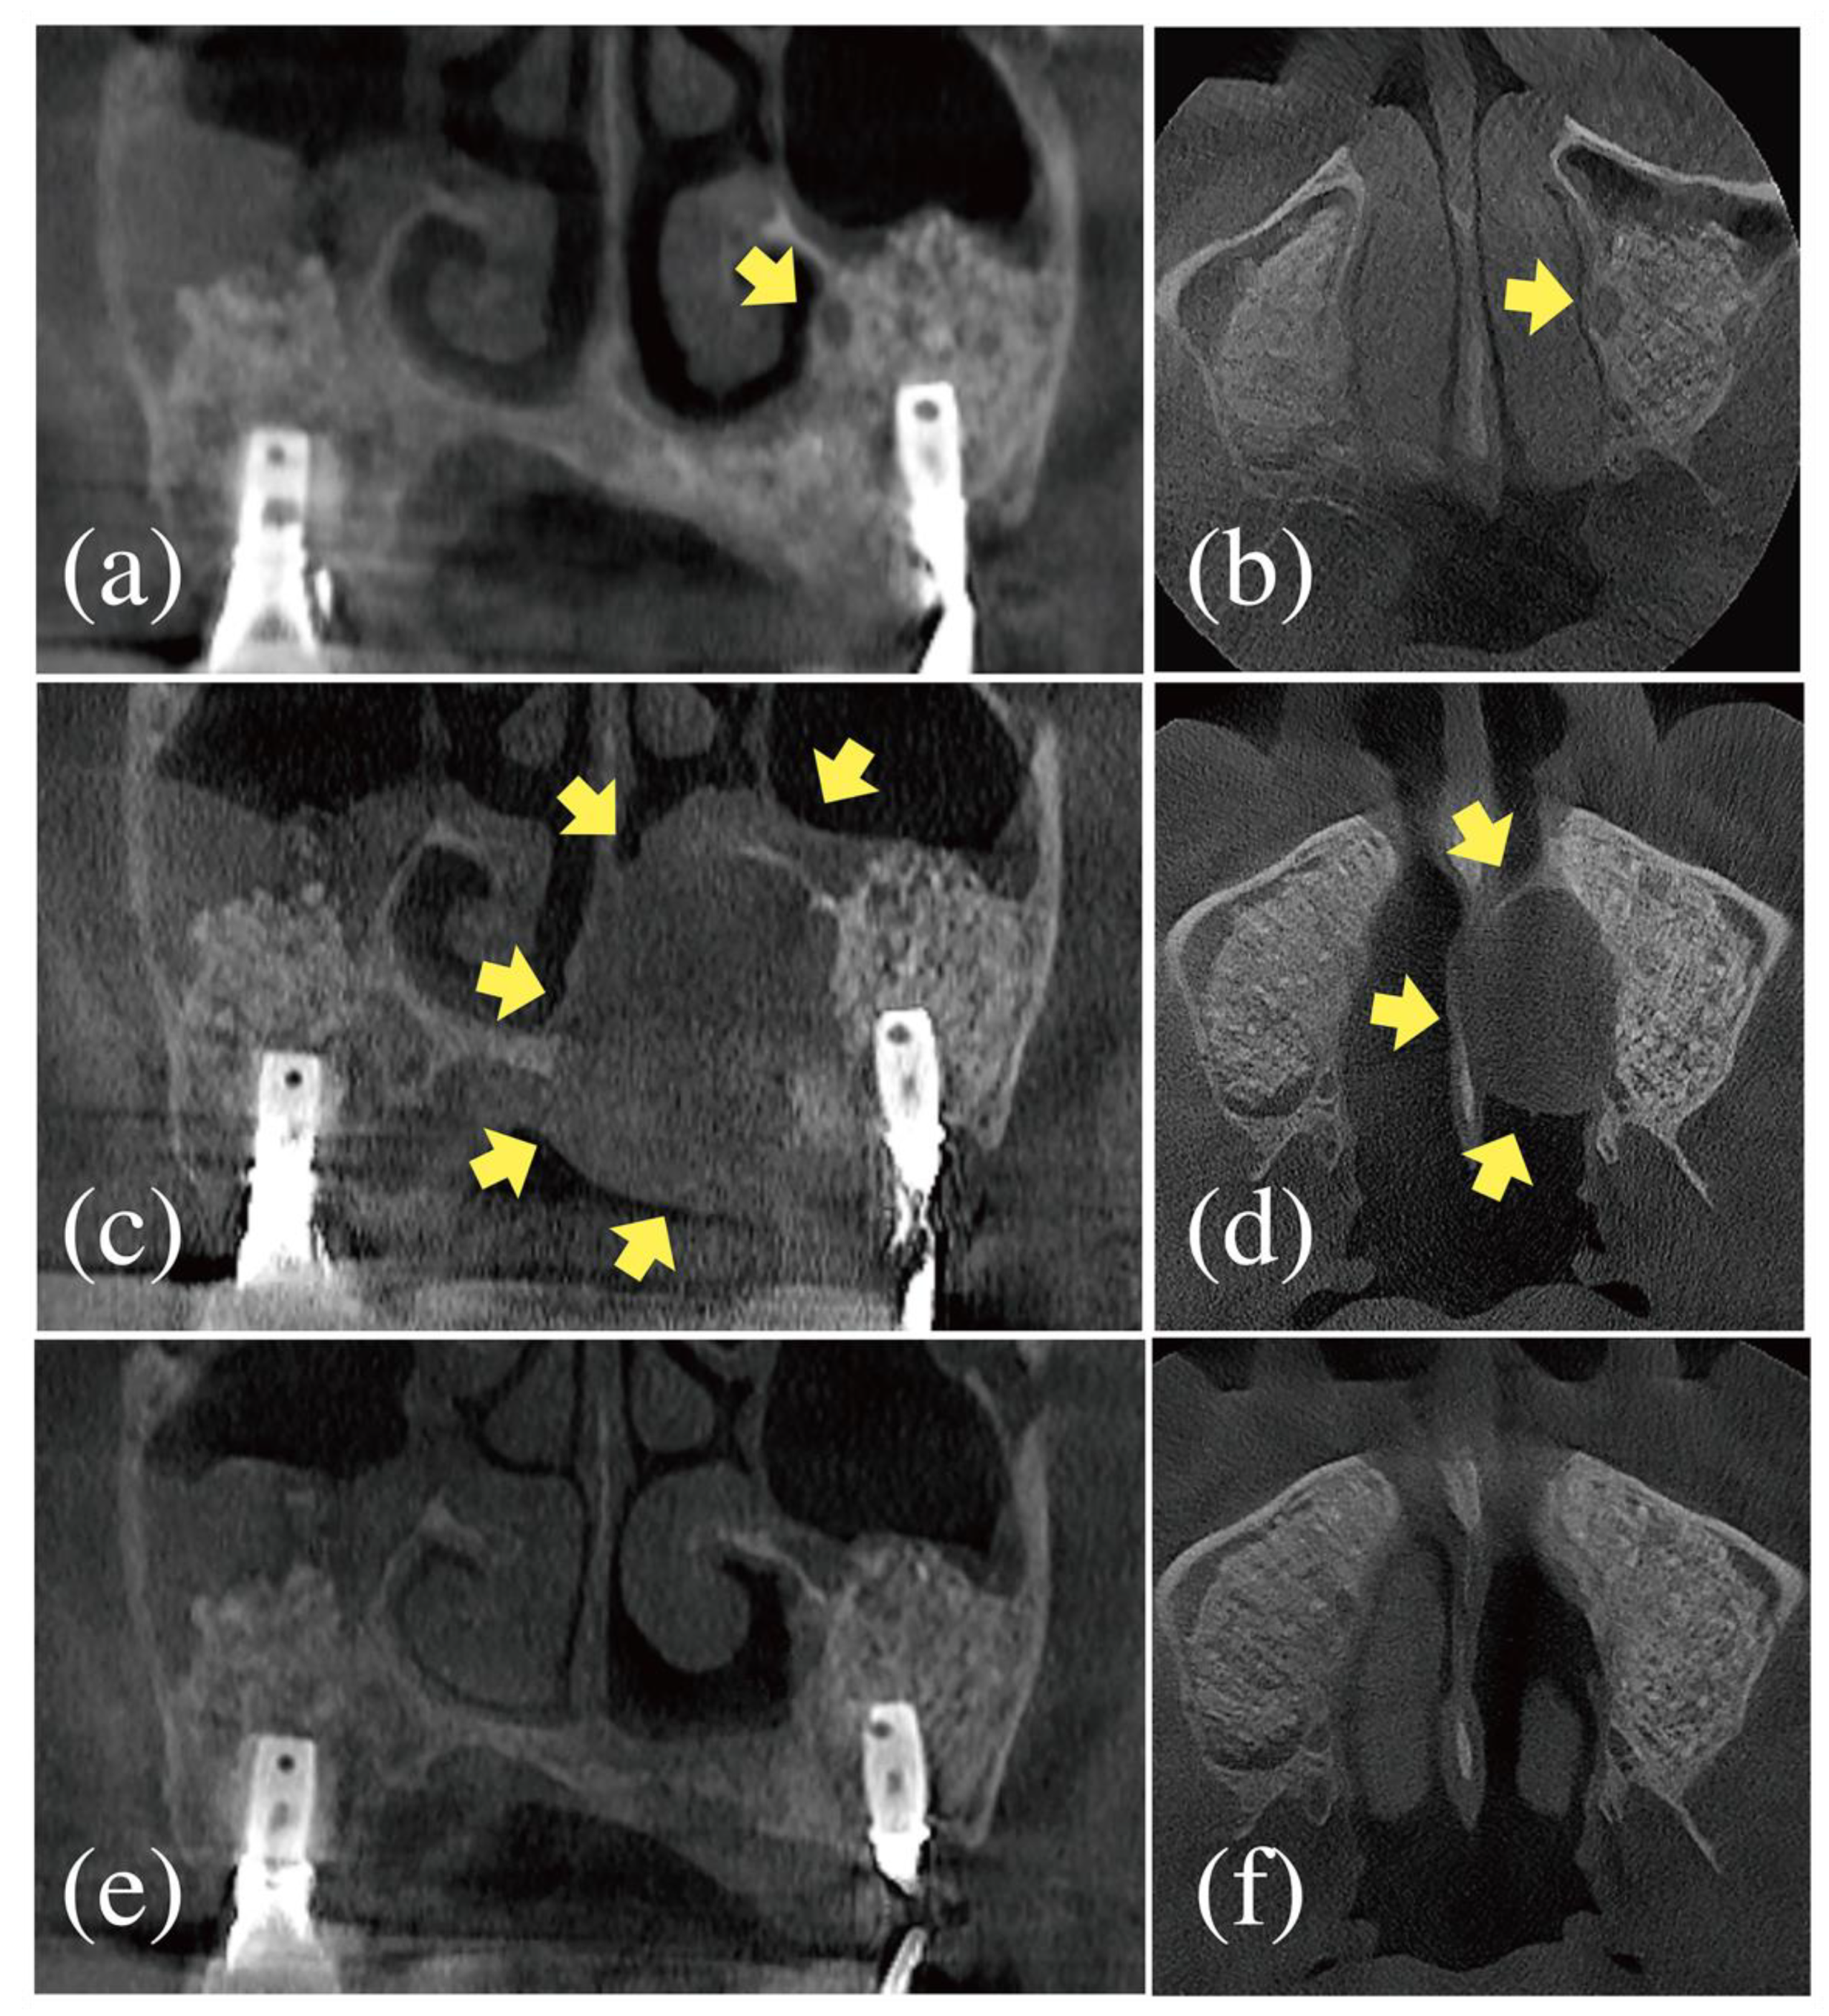

2.3. Referral to an Otolaryngological Specialist

2.4. Follow-Up